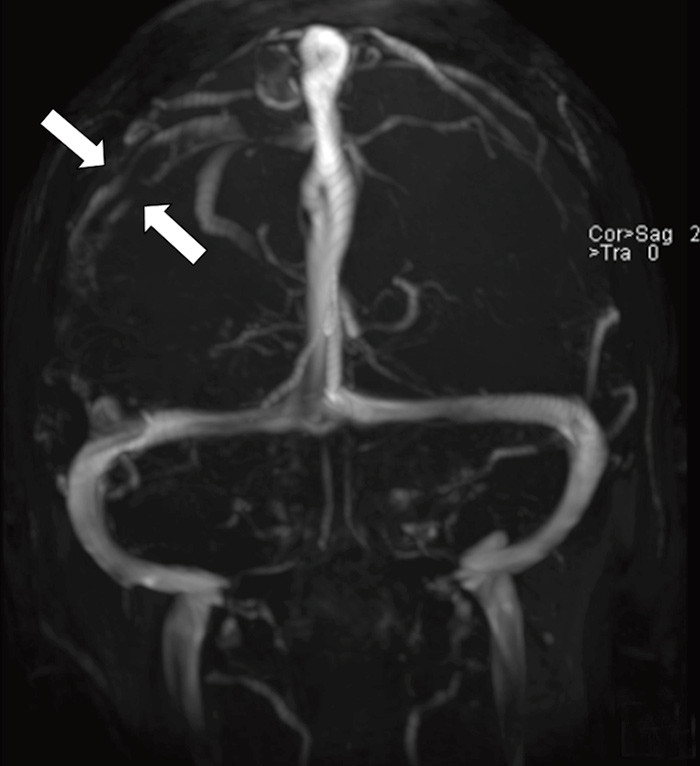

En tidligere frisk kvinne i 40-årsalderen hadde fra dagen før innleggelsen morgenhodepine og oppkast. Hun var ikke-røyker og brukte ingen medisiner eller hormoner. Innleggelsesdagen utviklet hun akutt parese i venstre ansiktshalvdel, venstresidig armparese og dysartri. Hun hadde forbigående rykninger i venstre ansiktshalvdel. Cerebral CT utført ved lokalsykehuset viste en høyattenuerende lesjon i høyre temporoparietallapp (bilde kun på nett). D-dimer var 0,8 mg/l (normalt < 0,4). Man mistenkte vaskulær hendelse i høyre hemisfære. Cerebral MR-venografi ved universitetssykehuset dagen etter viste en intraluminal venøs fyllingsdefekt svarende til høyre vena Trolard (bildet til venstre). Diffusjonsvektet cerebral MR viste en blanding av vasogent og cytotoksisk ødem temporoparietalt, typisk for venøst infarkt (bildet til høyre). Testing av forstyrrelser i trombose-koagulasjonssystemet viste aktivert protein C-resistens 0,66 (normalt 0,85 – 1,15). Pasienten fikk antikoagulasjonsbehandling og seks dager etter initiering av antikoagulasjon var ny cerebral MR-venografi normalisert. Hun ble utskrevet uten sekvele.

Cerebral venetrombose gir ofte hodepine, og kan gi nevrologiske utfall og epileptiske anfall ved samtidig infarktutvikling. Aktivert protein C-resistens disponerer for cerebral venetrombose, som er en sjelden (0,5 – 1 %) årsak til hjerneslag (1). Rask diagnostikk og behandling er vesentlig for prognosen. CT- og MR-venografi kan med høy sensitivitet og spesifisitet ikke-invasivt visualisere venøse cerebrale tromber.